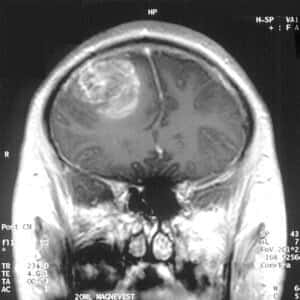

Glioblastoma is a type of brain cancer that is extremely hard to treat. People diagnosed with this condition usually survive for little more than a year.

Image Credited to Christaras A and licensed as Creative Commons Attribution-Share Alike 3.0 Unported